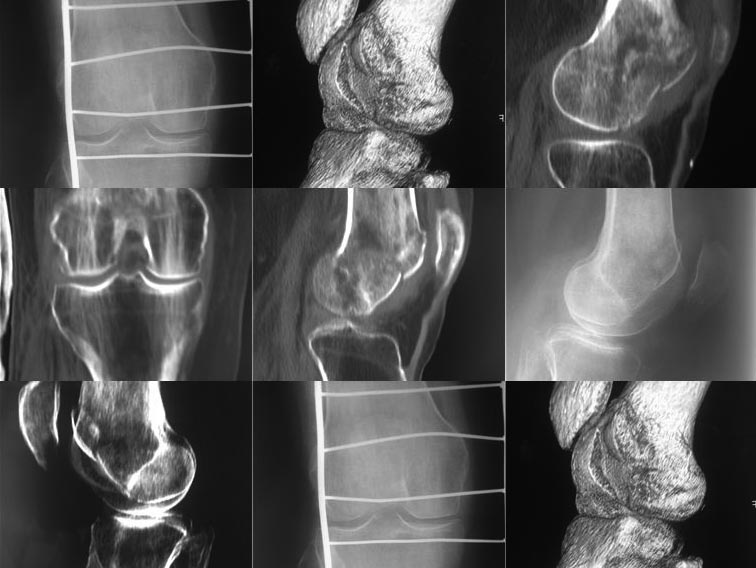

Поступила женщина 48

лет, внутрисуставной перелом латерального мыщелка бедра. Выполнили КТ.